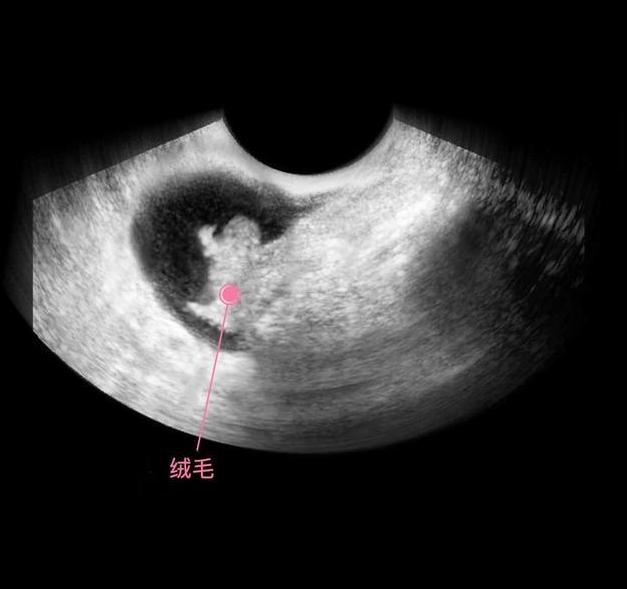

上图是怀孕后,受精卵经过了分裂,形成了细胞团,这个阶段还不能叫胎儿,只能叫胚泡,胚胎开始发育并分泌人体促绒毛性腺激素,不过此时的含量还很少,用验孕棒根本测试不出来。

上图可见子宫中的囊状结构,胎儿由两层的组织构成胚胎,所有的器官和组织都是有这些组织发育而成,胚胎羊膜囊的空腔中,开始有羊水积聚,为将来包裹和保护胎儿做准备。

细胞继续分化,有的分化成胎儿的大脑,有的分化成胎儿的肾脏和肝脏,还有的分化成心脏等,这个时期的宝宝叫做胎芽,依靠着卵黄囊提供的营养,还用不到母体的营养呢,所以此时有了怀孕反应,没有食欲也没有关系,对胎儿发育的影响不大。